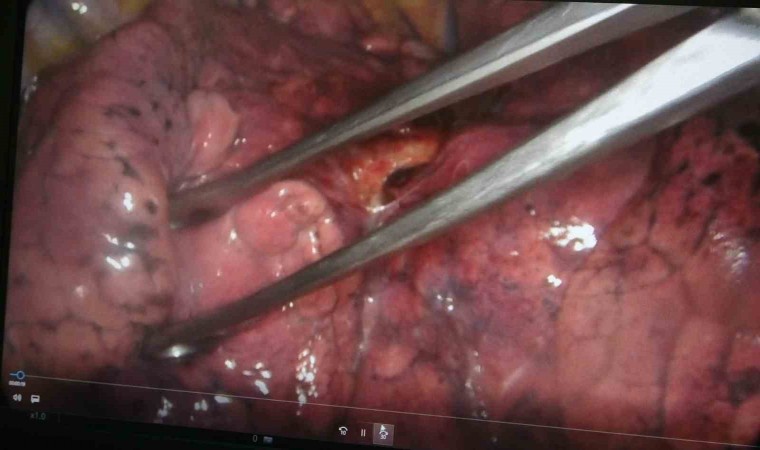

Doç. Dr. Onur Ermerak, "Akciğer kanseri, dünyada kanser nedenli ölümlerde en sık rastlanan ölüm nedenidir. Akciğer kanserinde henüz tarama aşamasına gelemedik. Amacımız o aşamaya gelip erken evrede akciğer kanserini yakalayıp o hastalığı tedavi etmeye başlamaktır. Akciğer kanserinin sigarayla ilişkili olduğunu biliyoruz. Çevre kirliliği, çeşitli kimyasallar akciğer kanserine neden olmaktadır. Maalesef geç bulgu ve şikayet verdiği için hastalar genelde geç evrede yakalanıp tedaviden yarar göremeyecek durumda bize başvuruyorlar. Sadece yüzde 15 hastada sağ kalım görülmektedir. Biz onu çok daha yüksek rakamlara çıkartıp hastalarımıza güzel günler sunmak istiyoruz. Öksürük, istenmeyen kilo kaybı, kanlı balgam, halsizlik, yorgunluk ve iştah kaybı gibi etkilerle görülmektedir. Özellikle kilo kaybı ve geçmeyen öksürük bizim için çok önemli bir bulgudur. Bu hastaların bize başvurmaları gerekir. Burada altını çizmek istediğimiz nokta, tarama programlarıyla sağ kalımda da yüzde 40’lara kadar bir artış sağlamaktayız. Tarama programı, düşük doz tomografilerle hastaları tarayıp bu hastalık daha oluşma aşamasındayken en güzel tedaviyi verip hastaların akciğer kanseri ile baş başa kalmamasını sağlıyoruz. 50 yaş üstünü geçmiş ve 15 yıl sigara tüketmiş hastaların hepsi tarama yapmalıdır. Bizim ülkemizde de aktif sigara kullanımının yanında pasif içicilik de devam ediyor ve biz bu konuyu ciddiye almalıyız. Akciğer kanserine yakalanan hastaların yüzde 90’ı sigara içmekte. Bunların arasında da yüzde 50’si sigarayı bırakmış hastalar oluyor. Hastaların merkezlere başvurup taramasını yapıp hastalığı erken evrede yakaladıktan sonra en uygun tedavilerle sağlığına kavuşmasını amaçlamaktayız. Sigara içmemek çok önemli. Sigara içilen ortamda dahi bulunmamaları çok önemli. Ve farkındalığı oluşturup en ufak bir şüphede gerekli tarama endikasyonlarıyla gidip taranmalarını öneriyoruz. Akciğer kanseri sinsi bir kanserdir, geç bulgu ve şikayet veriyor. Öncelikle sigara içmeyelim ve hastalığın taramasını mutlaka yaptıralım" dedi.